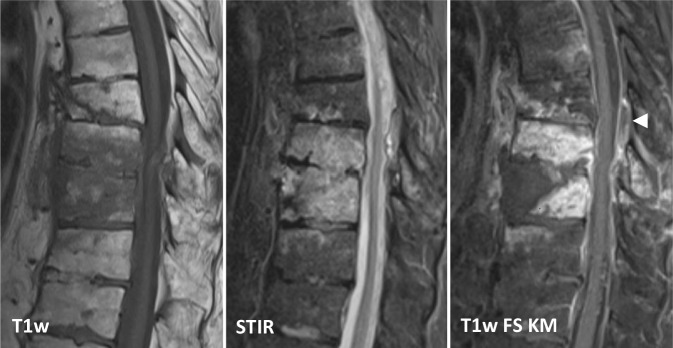

Die MRT ist mit einer Sensitivität von 96 %, einer Spezifität von 92 % und einer Genauigkeit von 94 % die Bildgebung der Wahl [4]. Noch vor knöchernen Destruktionen zeigt sich eine Zunahme des Flüssigkeitssignals der betroffenen Wirbelkörper und Bandscheiben im Sinne eines T1w-hypointensen, T2w-hyperintensen Ödems sowie in den T1-gewichteten Sequenzen eine Anreicherung von i.v.-Kontrastmittel (Abb. 2). Der Verlust des sog. „nuclear cleft sign“, einer T2w-Hypointensität der zentralen Bandscheibe, die von einigen als altersabhängig physiologischer Prozess, von anderen als erster Grad der Degeneration der Bandscheibe gewertet wird, kann mit einer Spondylodiszitis einhergehen, ist für eine solche jedoch nicht spezifisch [14].

Die Entzündungsreaktion lässt sich meist zunächst anterolateral im Wirbelkörper in der Nähe der Endplatten abgrenzen und zeigt nach Kontrastmittelgabe in T1-gewichteten Sequenzen eine teilweise inhomogene Kontrastmittel-Mehranreicherung. Das assoziierte Ödem betrifft hingegen typischerweise den größten Teil des Wirbelkörpers und der angrenzenden Bandscheibe [4]. Bei der tuberkulösen Spondylodiszitis bzw. Spondylitis kann die Bandscheibe weitgehend erhalten sein, da diese häufig vorrangig den Knochen, insbesondere die dorsalen Wirbelanteile, betrifft [15].

Einen Überblick über typische Befunde der pilzassoziierten Spondylodiszitis gibt Tab. 3.

| Wirbelkörper | Destruktion der Endplatten; T1w-Hypointensitäten, T2w-Hyperintensitäten, Anreicherung von i.v. Kontrastmittel; Osteolysen, Destruktionen, Erosionen |

| Paraspinalraum/Epiduralraum | Kleine paraspinale Abszessformationen; unscharf abgrenzbare Entzündungsreaktionen |

| Anteriore, subligamentäre Ausbreitung | Häufig |